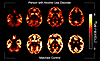

Synaptic density images by diagnostic group.Figure 2

Synaptic density images by diagnostic group. Parametric images of PVC BPND maps from 2 representative participants who were similar to the group.